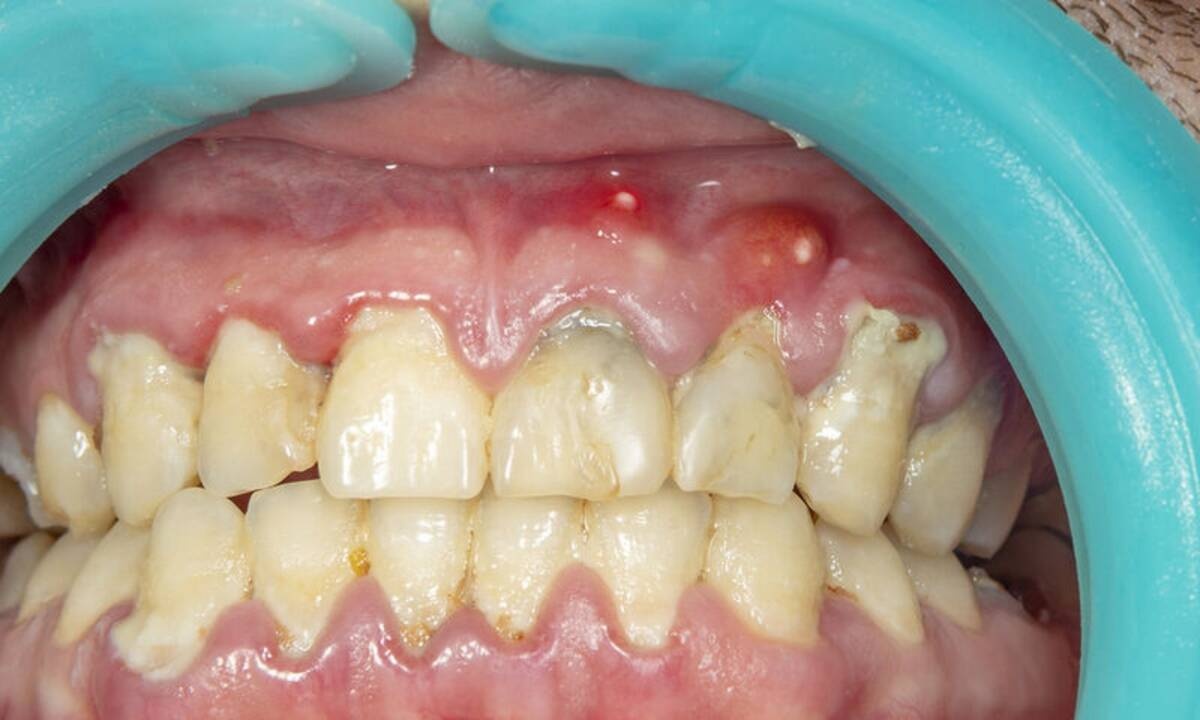

Η συγκέντρωση πύου στα ούλα ή στη ρίζα του δοντιού, που οφείλεται στην ύπαρξη φλεγμονής, ονομάζεται απόστημα.

Τα αποστήματα εμφανίζονται συνήθως μετά από οδοντιατρική χειρουργική επέμβαση, εξαιτίας λοίμωξης των ούλων, τραυματισμού ή φθοράς των δοντιών.

Τα συμπτώματα ενός αποστήματος είναι οίδημα στην περιοχή, έντονος πόνος και πικρή επίγευση κατά τη μάσηση ή κατά την πόση ροφημάτων, κακοσμία, ερυθρότητα και έντονο πρήξιμο των ούλων στην περιοχή του δοντιού με το πρόβλημα.